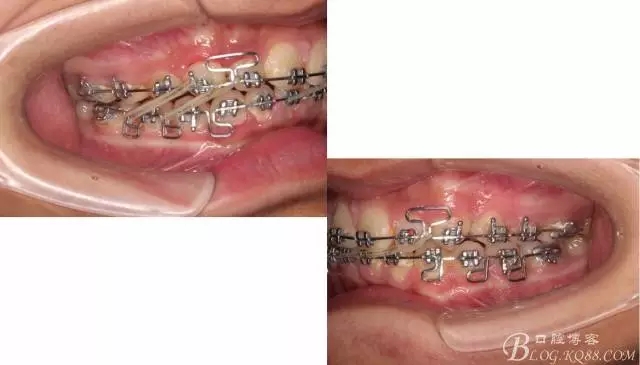

佩戴三個月的FR2, 效果奇佳!前牙基本達到淺覆蓋,淺覆合!接下來進入二期直絲弓固定正畸,排齊階段!

接下來盡管配合些雙側(cè)后牙對角牽引,咬合關系依,不盡人意。

下頜配合多曲方絲,三角牽引,調(diào)整咬合。